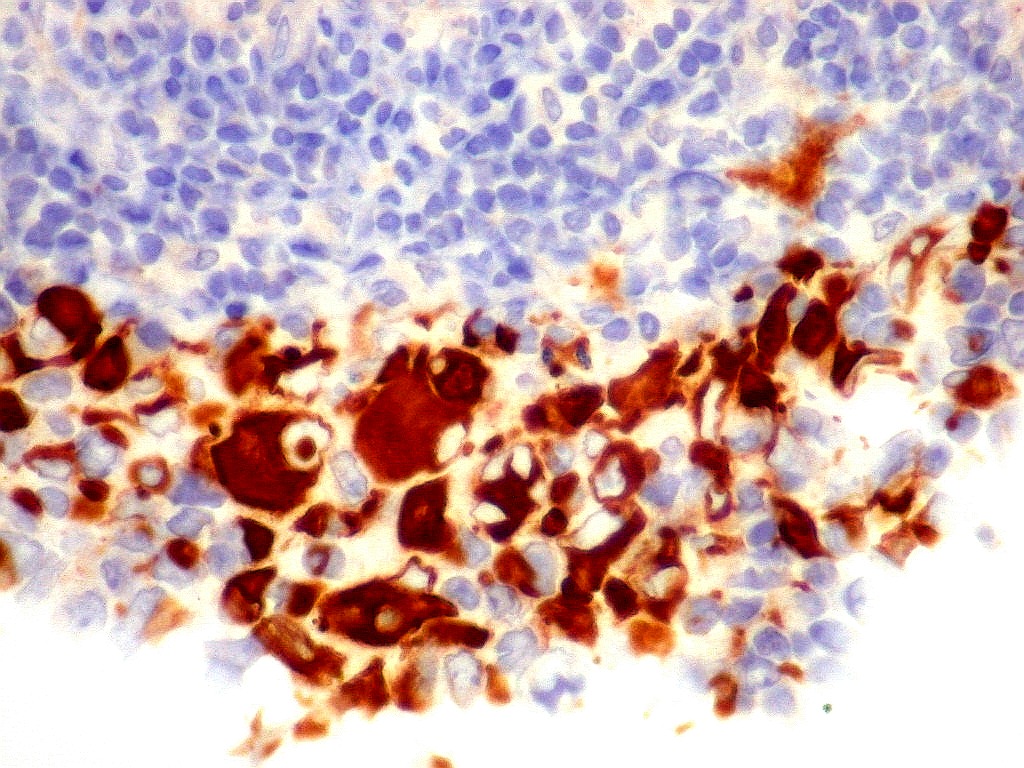

| AE1AE3. Pancitoqueratina, um coquetel para queratinas de alto e baixo peso molecular, indica linhagem epitelial das células neoplásicas. Aqui, fortemente positiva nas células tumorais, com controle interno negativo num folículo linfóide, constituído por linfócitos. Ver marcação para estes em CD3, CD20. Indica diferenciação epitelial. |

| EMA. Antígeno epitelial de membrana. Ocorre em epitélios, e também em células meningoteliais. Aqui fortemente positiva nas células deste tumor teratóide rabdóide atípico. Negativo no folículo linfóide incluído fortuitamente na amostra. Positivo também no epêndima do III ventrículo adjacente ao tumor. Notar que as células ependimárias são ciliadas. |

| F. 17a. Tumor teratóide rabdóide atípico de III ventrículo. RM | HE | VIM, GFAP | HHF35, desmina, 1A4 | AE1AE3, EMA |